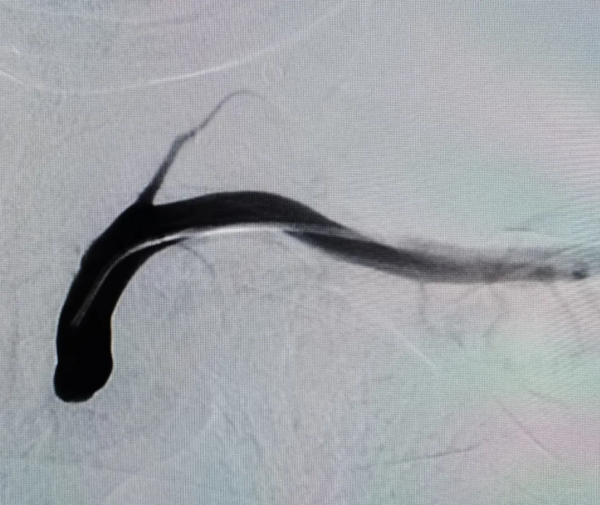

在前期充分準備的基礎上,由張志勇主任主刀歷時短短1.5小時,透過左側橈動脈入路,成功實現了左側鎖骨下動脈閉塞再通,術後患者左上臂血壓即刻恢復,頭暈症狀緩解。

術後造影顯示左側鎖骨下動脈再通,血流完全恢復 術後造影顯示左側鎖骨下動脈再通,血流完全恢復